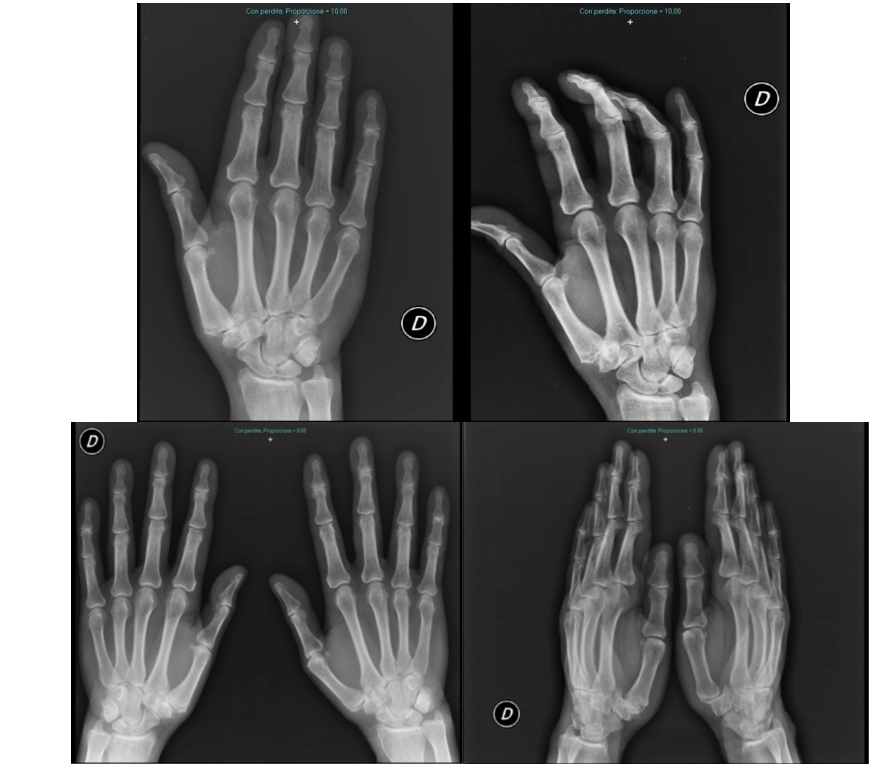

Introducing the case report of a 70-year-old man who came to our attention in 2017, at the “Ospedale Maggiore Carlo Pizzardi” in Bologna, complaining about trapeziometacarpal joint pain and related loss of function of the right thumb. Clinical symptomatology was characterized by activity-related pain and swelling localized at the base of the thumb. Clinical evidence documents positivity of the grind test and the traction shift. X-rays of both hands show bilateral rizharthrosis at third stage according to the Eaton classification (Table 1) [13].

Figure 1: X-ray pre operatory of right hand that shows Stage III according to Eaton and Littre classification.

Figure 2: X-Ray of Surgical treatment of trapeziectomy of right hand.

Figure 3: X-Ray post operatory right hand and confront both hands. Follow up 1 year.